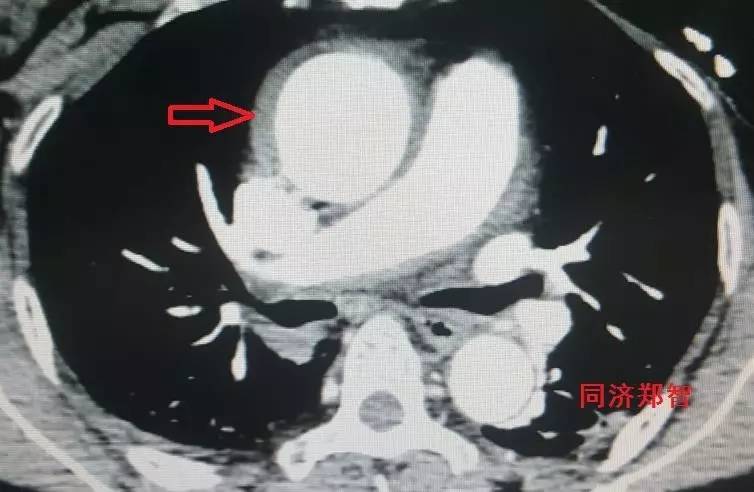

CTA轴位片显示主动脉弓穿透性溃疡(图11)。

图11